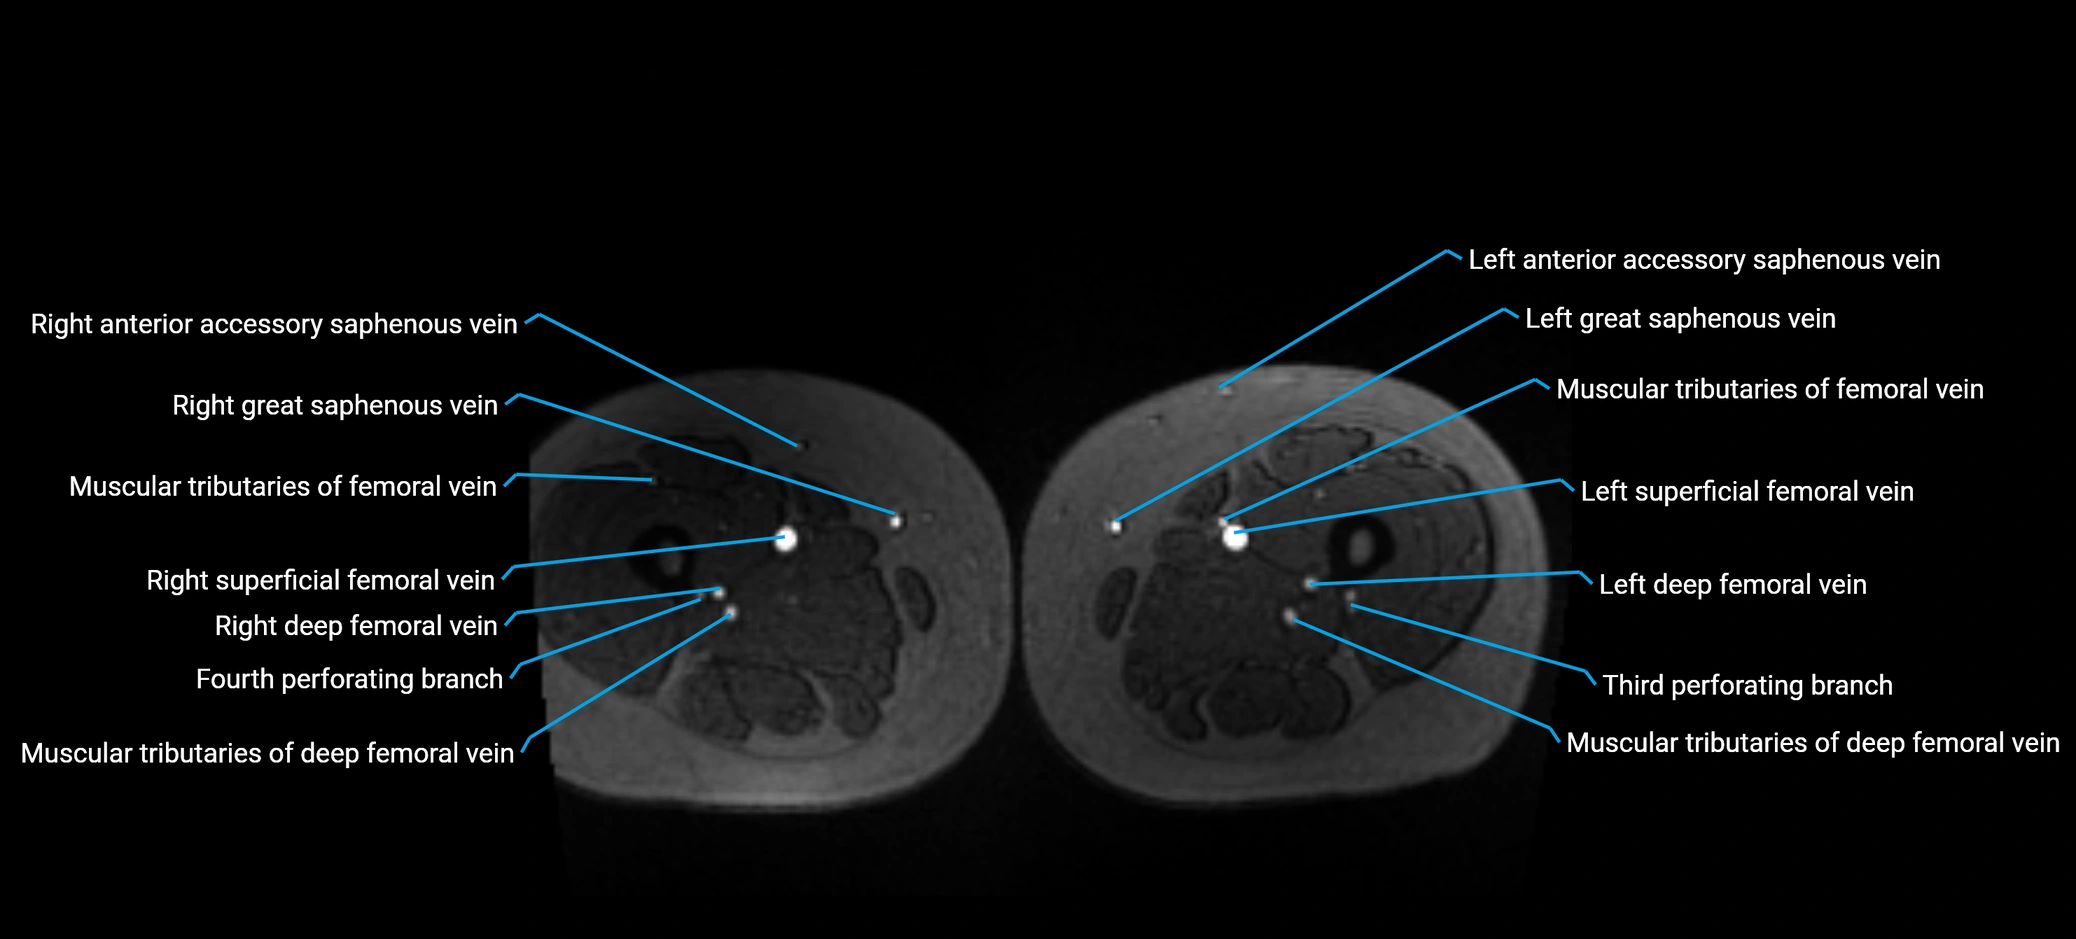

MRI image

image